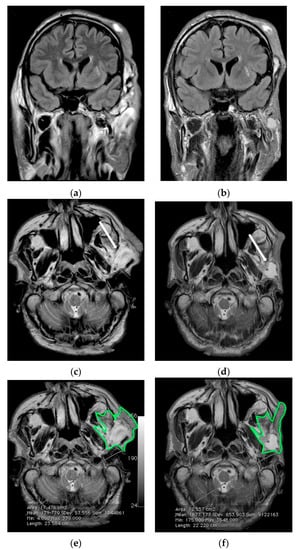

| MedDiet | 3 E.M. | 27 | M | yes | no | yes | yes | yes | yes | yes | no | no | yes | no | Fusiform aneurysms of both ICAs (ref) |